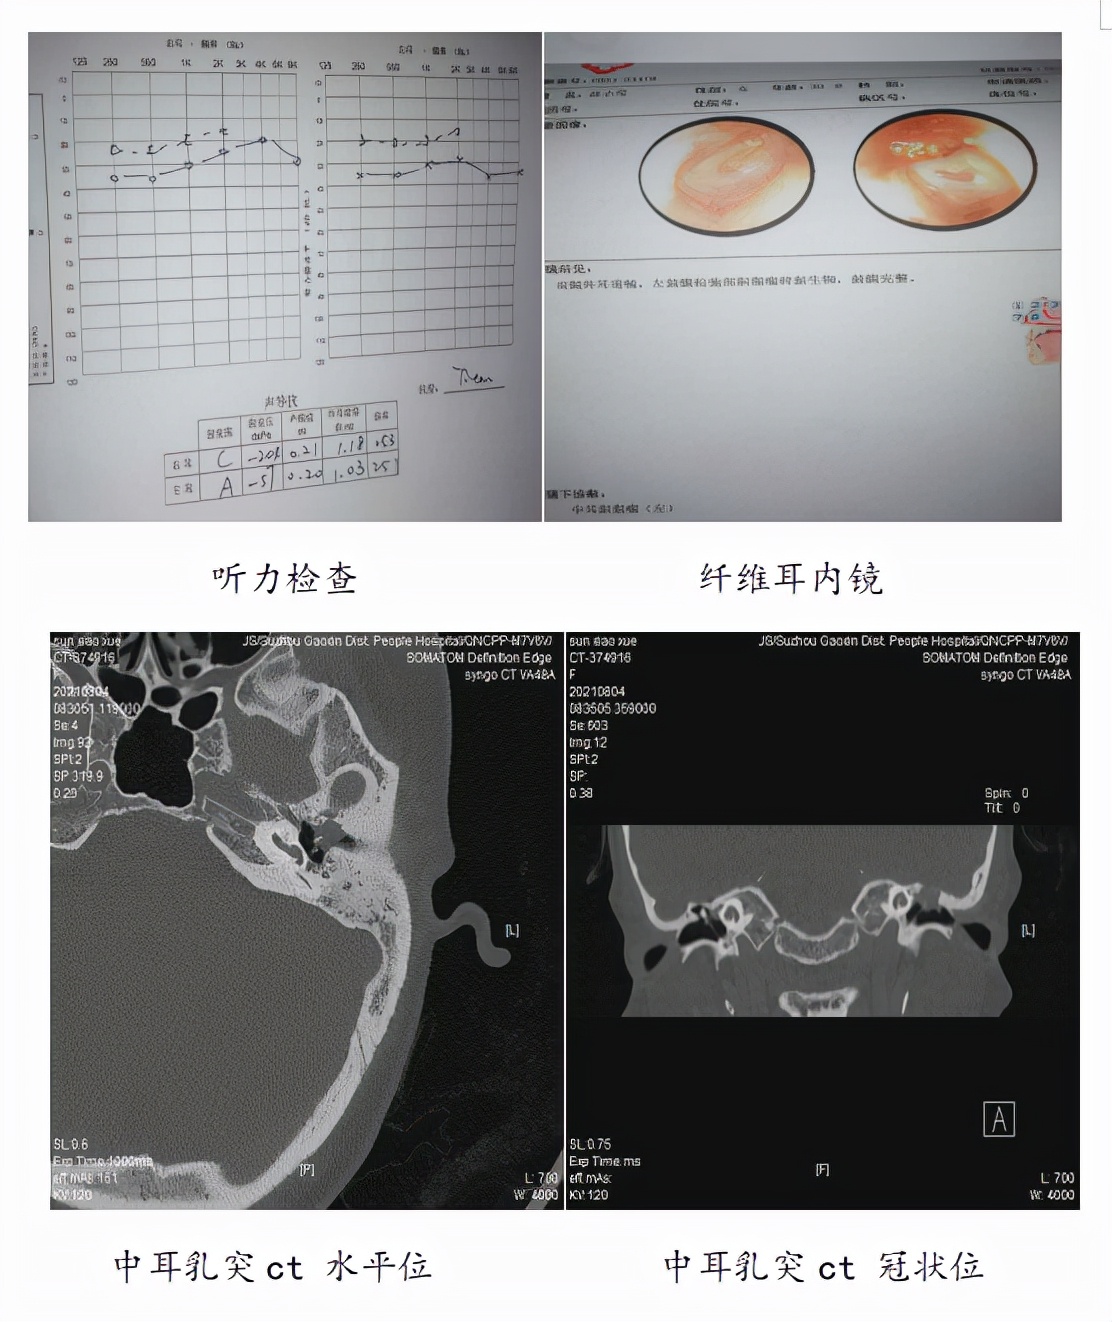

王鑫教授介绍说,当时给孙女士做了硬性耳内镜检查,发现患者左耳鼓膜内陷,鼓室内好像有白色团状东西,怀疑患者可能是咽鼓管功能障碍导致继发性中耳胆脂瘤。随即让患者进行了中耳乳突CT检查,发现左侧鼓室胆脂瘤,局部骨质破坏肿物向中颅窝膨隆,需要手术治疗。完善术前检查后,次日,在全麻下显微镜下为孙女士做了左耳乳突根治、鼓室成形手术。手术1月后,患者左耳恢复正常。